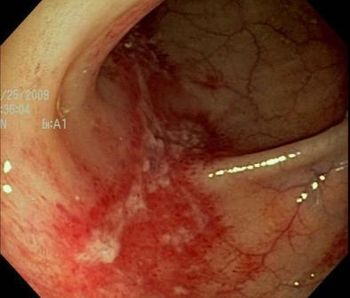

A medication change? Repeat colonoscopy with chromoendoscopy? Colectomy? Other?

See if the results of this 62-year-old woman's colonoscopy help you identify the source of her abdominal pain.